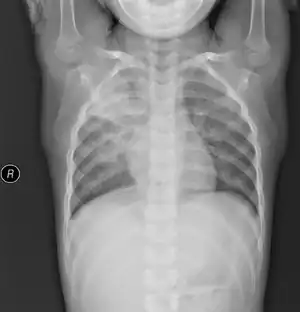

Mycoplasma pneumonia

Mycoplasma pneumonia (also known as "walking pneumonia") is a form of bacterial pneumonia caused by the bacterial species Mycoplasma pneumoniae. It is also known as PPLO, which is an acronym for Pleuro Pneumonia Like Organism.